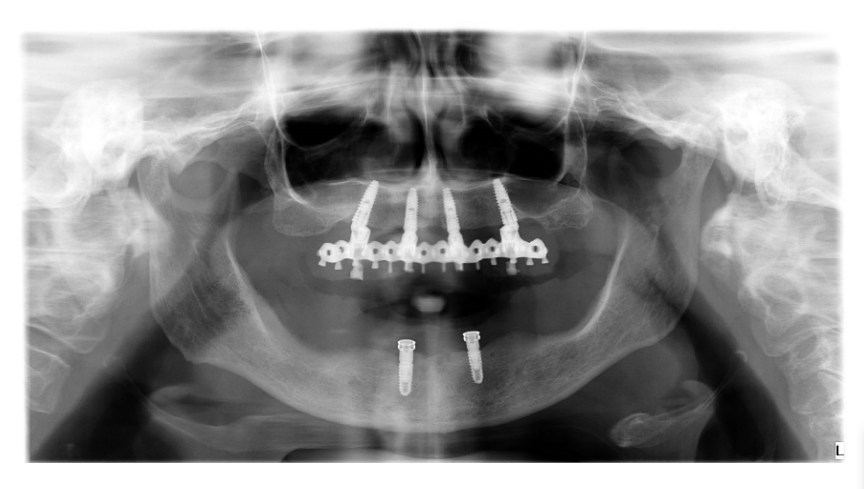

На этом этапе все последующие шаги, от планирования имплантации до доставки окончательных реставраций, были выполнены полностью в цифровом формате. После изготовления новых протезов пациенту был выполнен КТ-сканирование верхней и нижней челюстей по модифицированной технике двойного сканирования. Для последнего на нижнем протезе были применены трехмерные композитные маркеры, а для разделения зубных дуг использован восковый прикус. После этого было выполнено второе сканирование только нижнего протеза с использованием интраорального сканера (Medit i500). В нижней челюсти были запланированы два прямых импланта (Рисунок 4) и установлены (Рисунки 5 и 6) для удержания классического надпротеза.

В верхней челюсти было запланировано четыре имплантата по протоколу All-on-4 (Рисунок 7), чтобы поддерживать фиксированный, винтовой, зубной протез. Кроме того, также было запланировано уменьшение костной ткани верхней челюсти на три-четыре мм.

Имплантаты нижней челюсти были запланированы и установлены параллельно, и на имплантаты сразу же были прикручены соединения OT Equator (Rhein’83, Болонья, Италия). Лоскут был зашит, и окончательная надстройка была подключена к системам крепления на кресле. Через неделю, при удалении швов, имплантаты были нагружены. В верхней челюсти была изготовлена временная реставрация с металлическим усилением, основанная на протезном наборе, до операции (Рисунок 9).